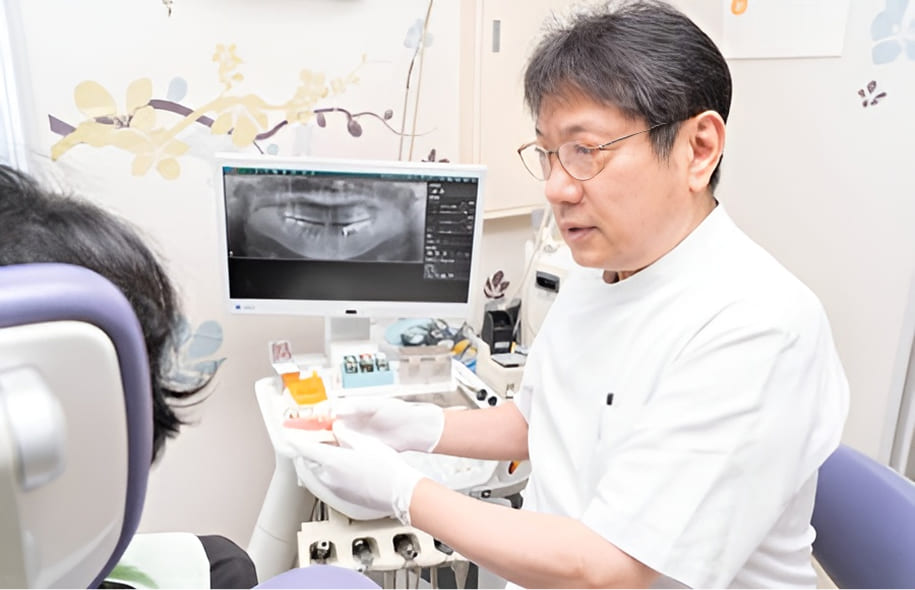

定期的に歯科医院で診てもらい

むし歯を予防・治療しましょう

ごく初期のむし歯の場合、進行を防ぐ適切な処置を施すことで、歯を削ることなく治すことが可能です。ただし、この段階での自覚症状がほとんど無いため、歯科医院で定期的な健診を受けるなどして、早期発見・治療を心がけることがむし歯の予防に繋がります。日頃からむし歯にならない口内環境を整えていきましょう。

予防歯科とは、虫歯や歯周病になる前の歯を予防し、大切にしていく処置です。歯とお口の健康を守るために、歯科医院などでのケアに加えて、歯科医師や歯科衛生士の指導に基づいたセルフケアをご自宅でも行い、予防歯科をしっかり実践していきましょう。適した予防のためにはこのどちらもが欠けてはならず、歯科医院で定期検診を受けていただくのが大前提です。

近年、ようやく日本でも予防歯科の重要性が注目されてきていますが、すでに欧米では歯科医院などで定期検診を受けることが習慣付いています。常日頃から歯科医師や歯科衛生士と一緒に、歯とお口の健康作りを心がけていきましょう。

予防歯科の基本は、歯が生え始めた時から歯の健康を考えておくことにあります。歯を失うと生活の質が下がってしまうため、そうならないためにも日頃から正しい知識を身につけ、歯をトラブルから守り、管理することが重要です。健康な歯とお口でいるために、ぜひ予防歯科を始めましょう。

定期検診のペースについては、当院からは半年に1度の頻度でのご来院をお勧めしています。症状が進行している場合や気になることがあれば、3か月に1度のペースでご来院ください。